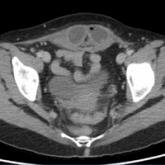

A 31-year-old man presented for evaluation of abdominal and rectal pain and episodic bloody diarrhea.

A 45-year-old woman presented for evaluation of abdominal pain.